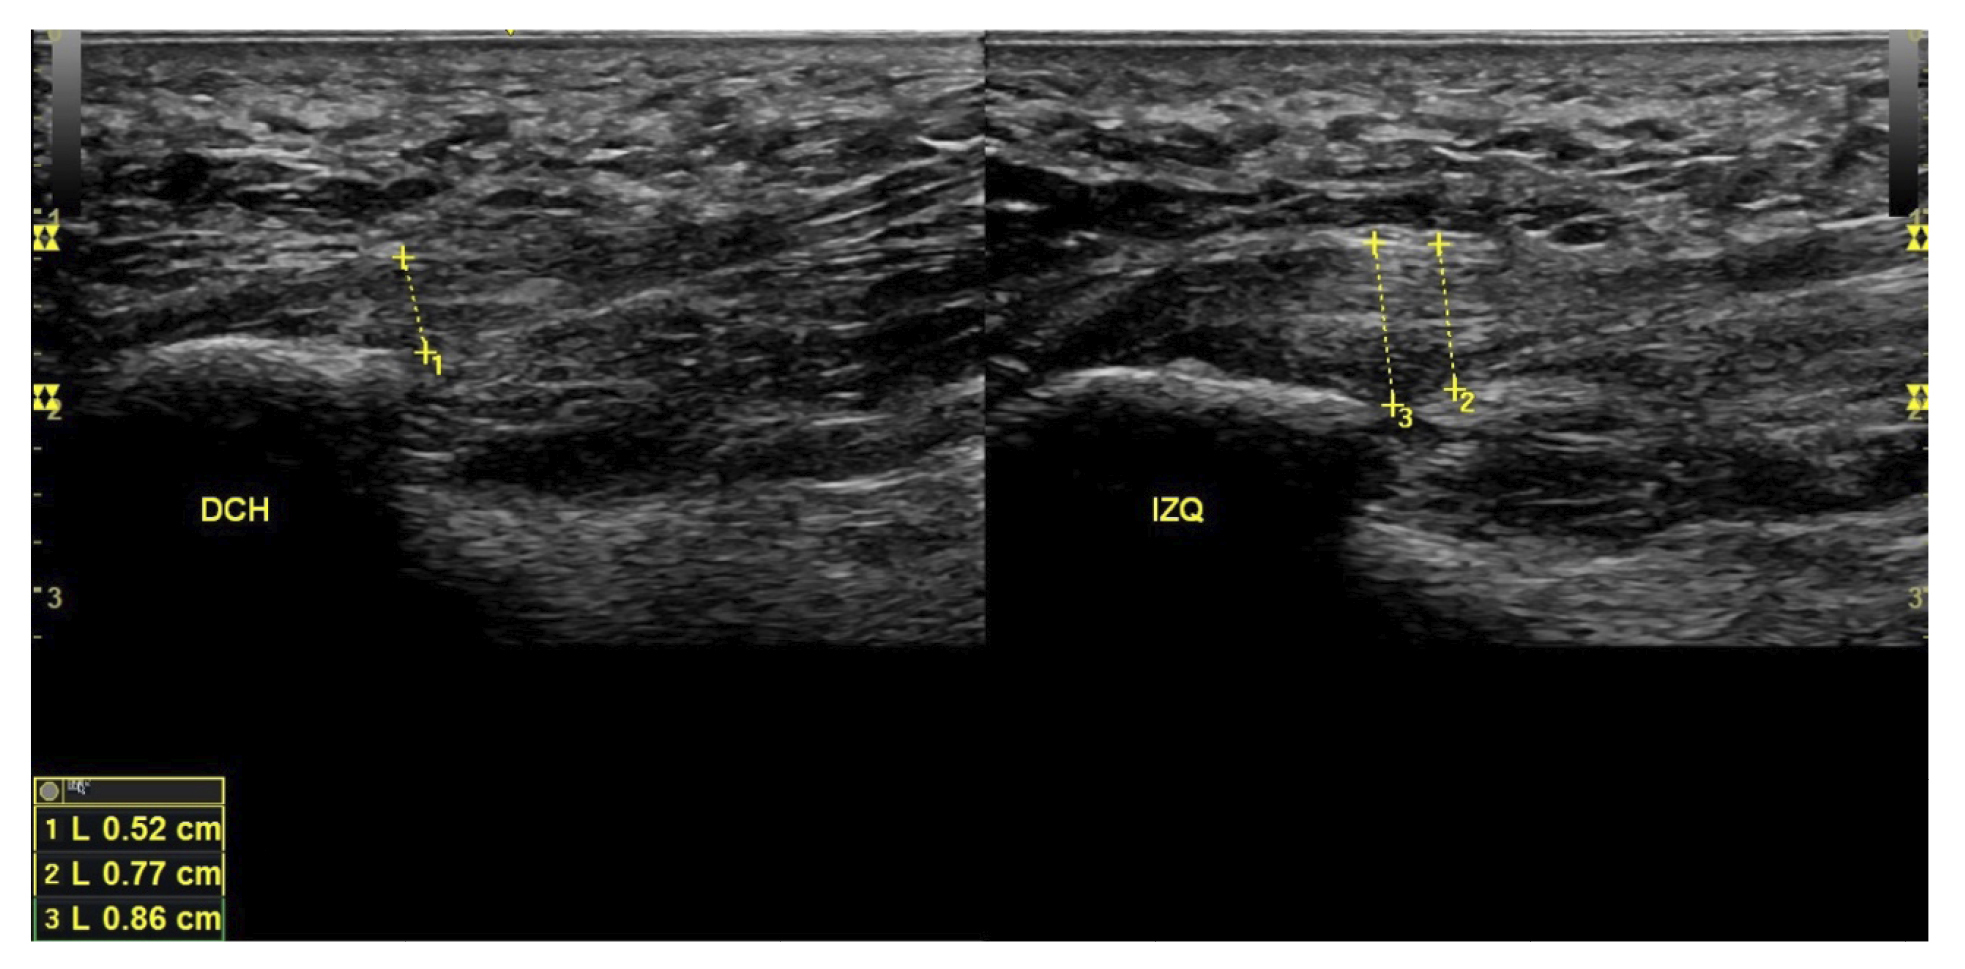

All patients underwent a clinical evaluation and an ultrasound evaluation. The clinical evaluation was based on a visual analog scale (VAS) (13) (0-10) and the Foot Function Index (FFI) (14,15), which assesses function on a scale of 0 to 100. Subjects were also classified as sedentary, active, or athletes based on their daily physical activity, as well as whether it was the first time the disease appeared, a recurrence, or chronic(16). Sex, weight, and height were also evaluated, as well as the presence of vascularization in the plantar fascia visualized with ultrasound at the time of the initial evaluation and the biconvex17 or flattened shape of the plantar fascia (Figure 1).

Figure 1. Plantar fascia with normal morphology on the left and biconvex plantar fascia on the right.

All patients had experienced the classic symptoms of PF, including pain when taking the first steps after waking up or after sitting for a long time. Patients felt pain upon palpation of the proximal plantar fascia and reported that the pain worsened as the day progressed. The diagnosis was established based on symptoms and confirmed by ultrasound using high-resolution equipment (Alpinion Ecube 9, ALPINION MEDICAL SYSTEMS Co., Ltd., Republic of Korea) with a 6-12 MHz linear transducer (Figures 2 and 3).